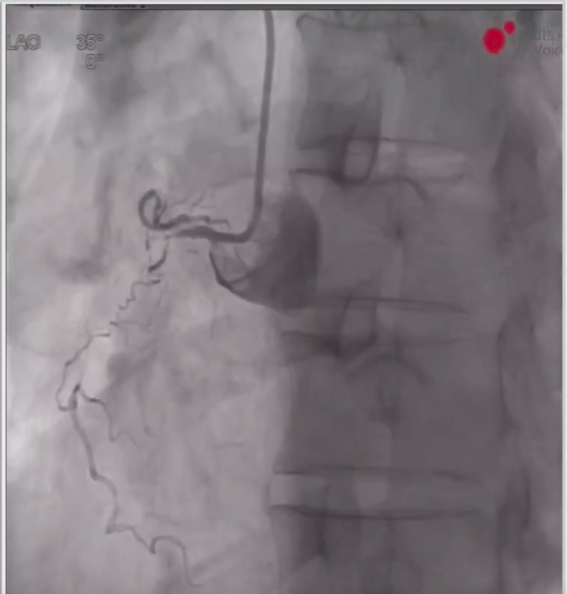

1、术前造影显示LAD近中段弥漫病变,LCX中段完全闭塞,RCA近段完全闭塞、远端形成侧枝循环。

LAD、LCX造影结果

RCA远端侧枝循环

RCA近端完全闭塞